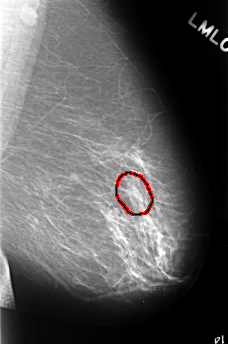

FILE: C_0390_1.LEFT_MLO.OVERLAY

TOTAL_ABNORMALITIES 1

ABNORMALITY 1

LESION_TYPE CALCIFICATION TYPE PLEOMORPHIC DISTRIBUTION CLUSTERED

ASSESSMENT 4

SUBTLETY 4

PATHOLOGY BENIGN

TOTAL_OUTLINES 1

BOUNDARY